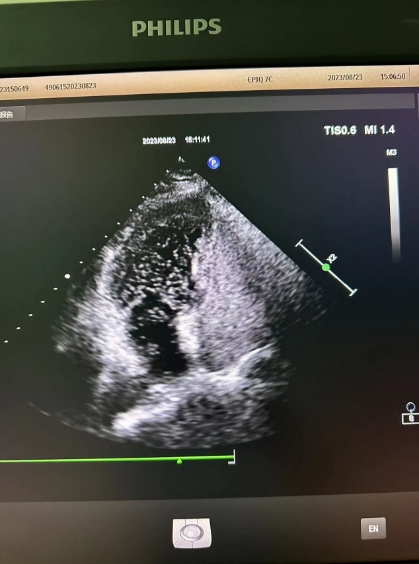

超聲心動圖檢查發(fā)現(xiàn)可能存在卵圓孔未閉,經(jīng)心內(nèi)科會診,詳細(xì)詢問病情、仔細(xì)了解病史后,為進(jìn)一步明確診治,決定為患者進(jìn)行右心聲學(xué)造影檢查。右心聲學(xué)造影是一項(xiàng)無創(chuàng)、便捷的超聲檢查技術(shù),醫(yī)護(hù)人員首先在患者胳臂上建立一個靜脈通路,然后把含有微小氣泡的振蕩生理鹽水注入患者體內(nèi),同時將超聲探頭放在患者心前區(qū),借助超聲檢查設(shè)備,觀察進(jìn)入人體心腔的微小氣泡運(yùn)動情況。

患者檢查后果然發(fā)現(xiàn)了異常,從屏幕上可以清晰看到,患者左心房內(nèi)很快出現(xiàn)了大量微小氣泡,這說明該患者的心臟存在著房水平由右向左的分流,提示有先天性卵圓孔未閉!根據(jù)這一檢查結(jié)果與患者及家屬溝通后,心內(nèi)科為其進(jìn)行了卵圓孔未閉封堵術(shù),最終改善了患者多年來的頭暈頭痛癥狀。